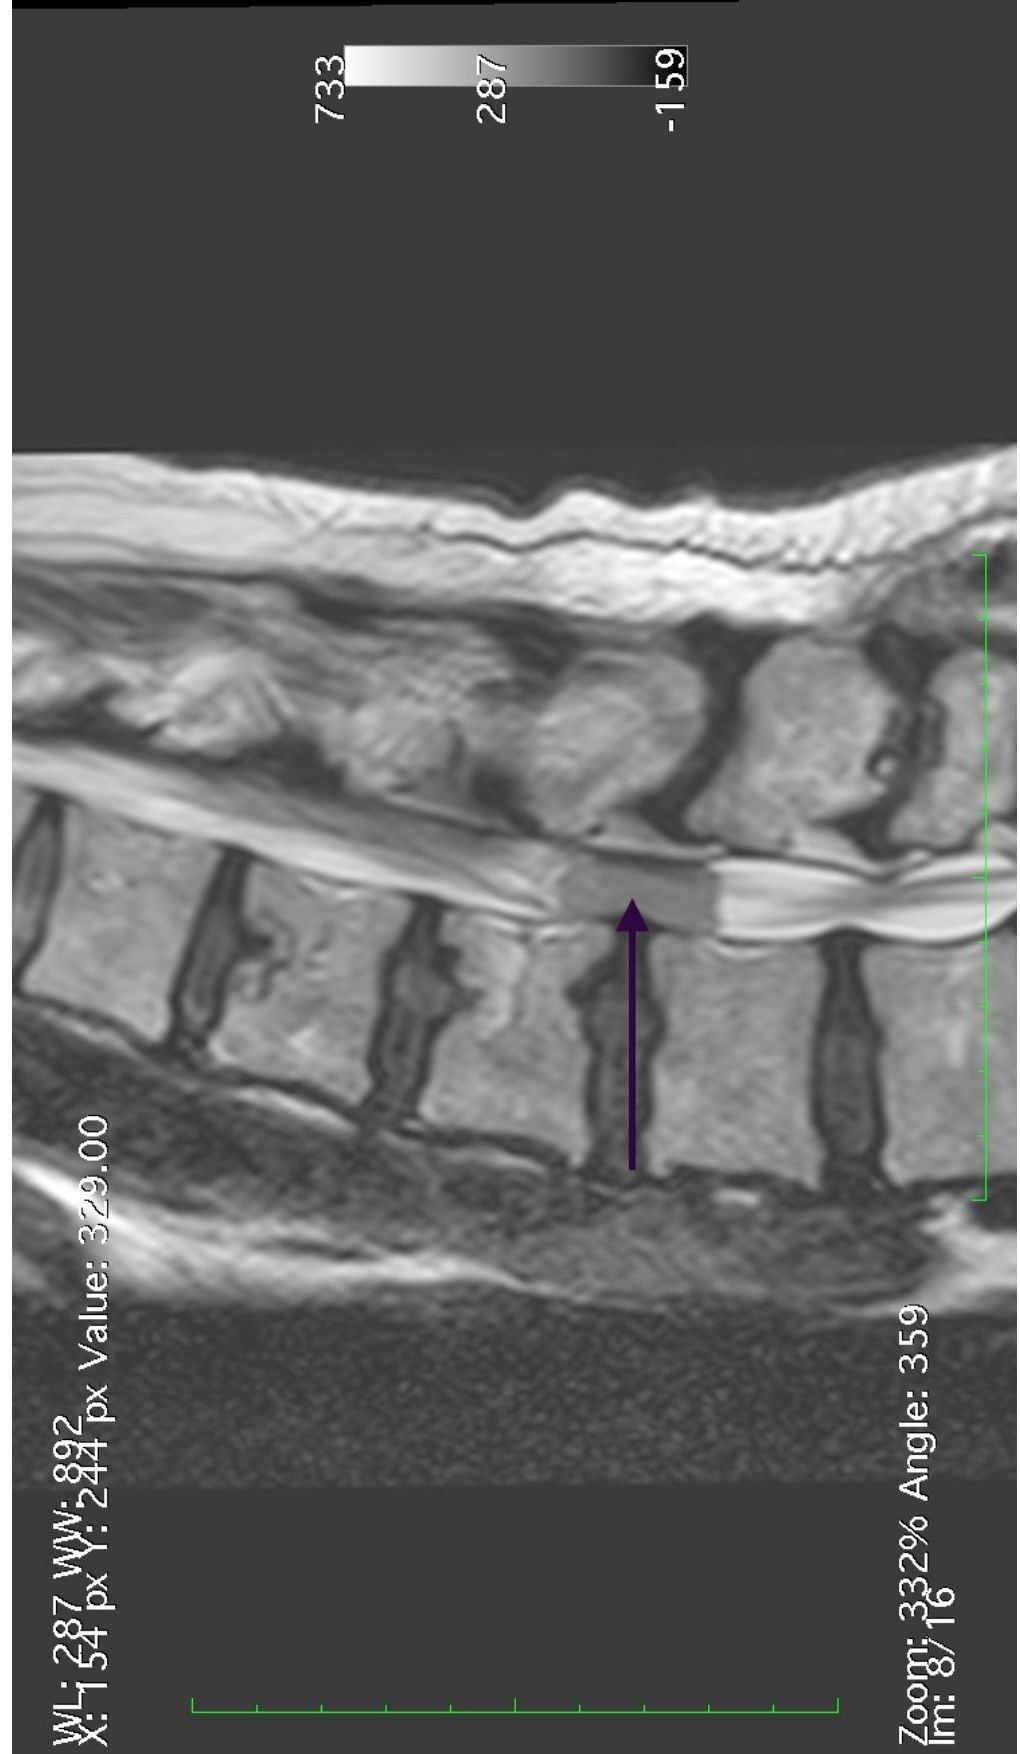

Patologia Degenerativa da Coluna Vertebral

- Tratamento de doenças que afetam a estrutura e função da coluna, com potencial impacto na qualidade de vida.

- Hérnia discal

- Traumatismo Craniano, Cervicalgia, Ciática e Lombalgia

- Fraturas osteoporóticas das vértebras